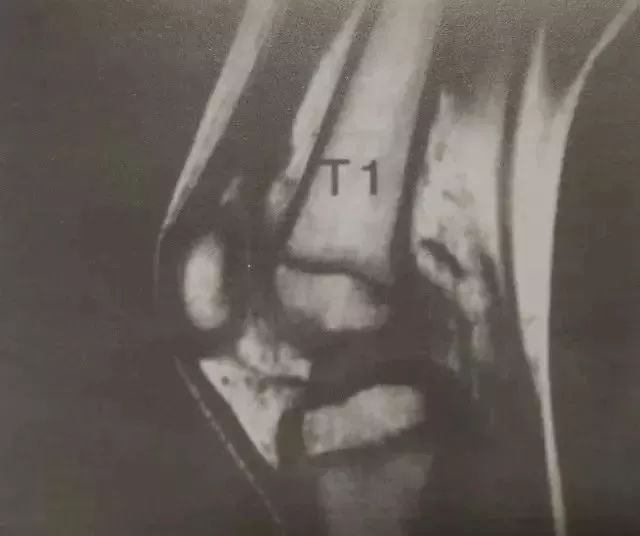

3。MRI

△急性前交叉韧带撕裂的MR图像

请注意,信号强度在股骨con和胫骨平台的软骨下区域增加,这些“骨瘀伤”的重要性尚不清楚。

一个。没有必要诊断前交叉韧带损伤,但是可以评估综合损伤。